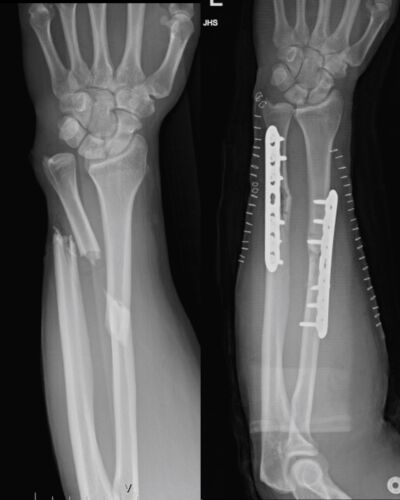

My son was seen for a broken arm. Everyone was very kind and patient with him, as this was a new experience for us. I am very pleased with the service we received and for a healed arm.